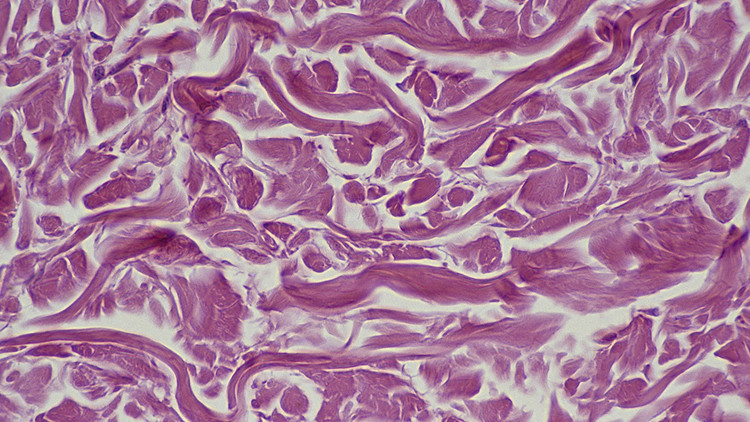

* Skar dokusu geriliyor: Fibrozis göstergeleri (sertleşme/skarlaşma) geriliyor.

Bu tablo, yaşlılıkla birlikte daha sık görülen yağlı karaciğer, fibrozis ve metabolik bozulmalar gibi sorunlara karşı uzun vadede yeni bir kapı aralayabileceği için önemli.